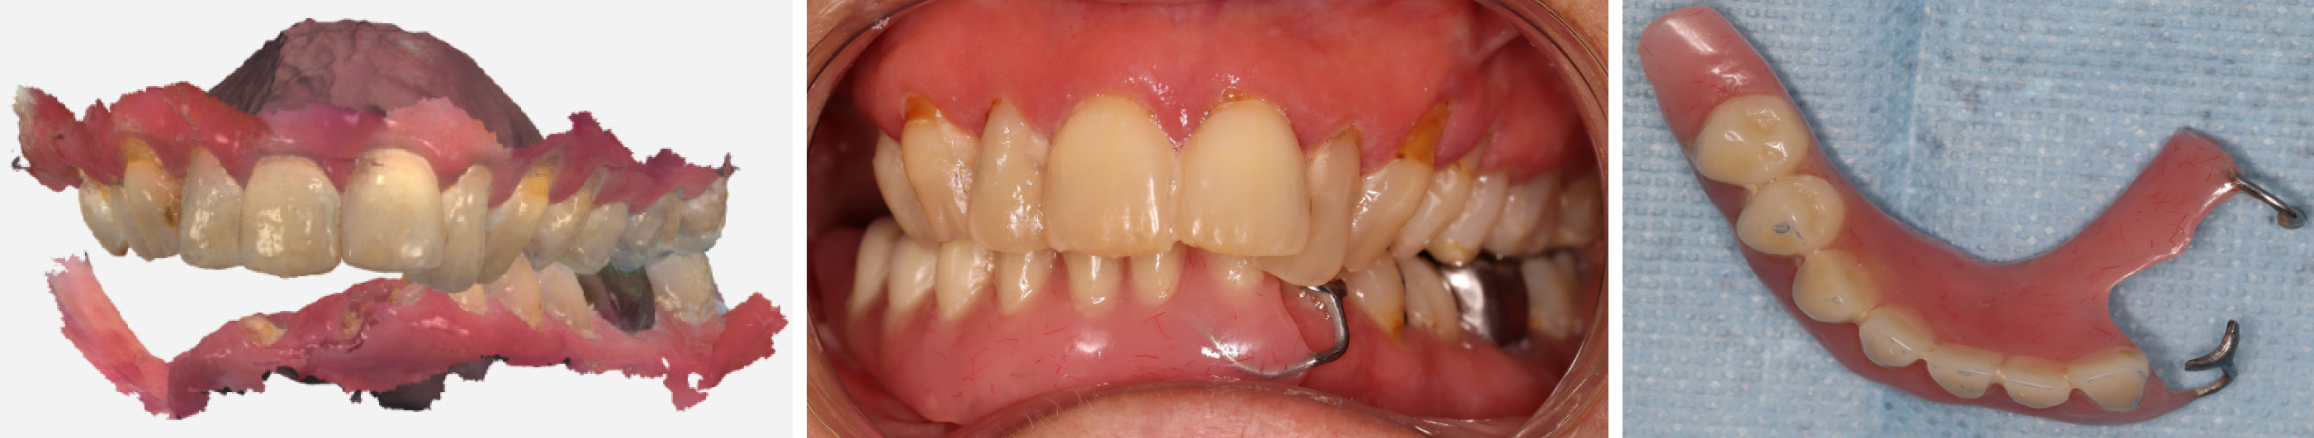

Extraoral examination revealed marked facial asymmetry, with soft tissue collapse of the right cheek and loss of support in the right lower lip. Intraoral examination showed severe trismus, with a maximum mouth opening of 15 mm. Generalized gingival inflammation and poor oral hygiene were noted, along with substantial, extensive plaque accumulation, thick and scanty saliva, and a posterior mandibular edentulous space at tooth 43. Root remnants were present at teeth 16, 17, 31, 32, 41, and 42, accompanied by multiple carious lesions (Figure 1).

Radiographic evaluation confirmed the stability of the mandibular reconstruction with no evidence of malignant recurrence. However, due to restricted mouth opening, retroalveolar imaging was challenging. Panoramic and periapical radiographs revealed widespread carious lesions on teeth 15, 14, 13, 12, 11, 21, 22, 23, 24, 26, 33, and 37 (Figure 2).

Dental diagnoses included extensive post-radiation carious lesions and external root resorptions, Kennedy-Applegate class II edentulism (posterior unilateral edentulism[24]), radiation-induced trismus, gingivitis, xerostomia, and soft-tissue deficits following surgical resection and facial asymmetry. These factors contributed to functional impairment and aesthetic problems.